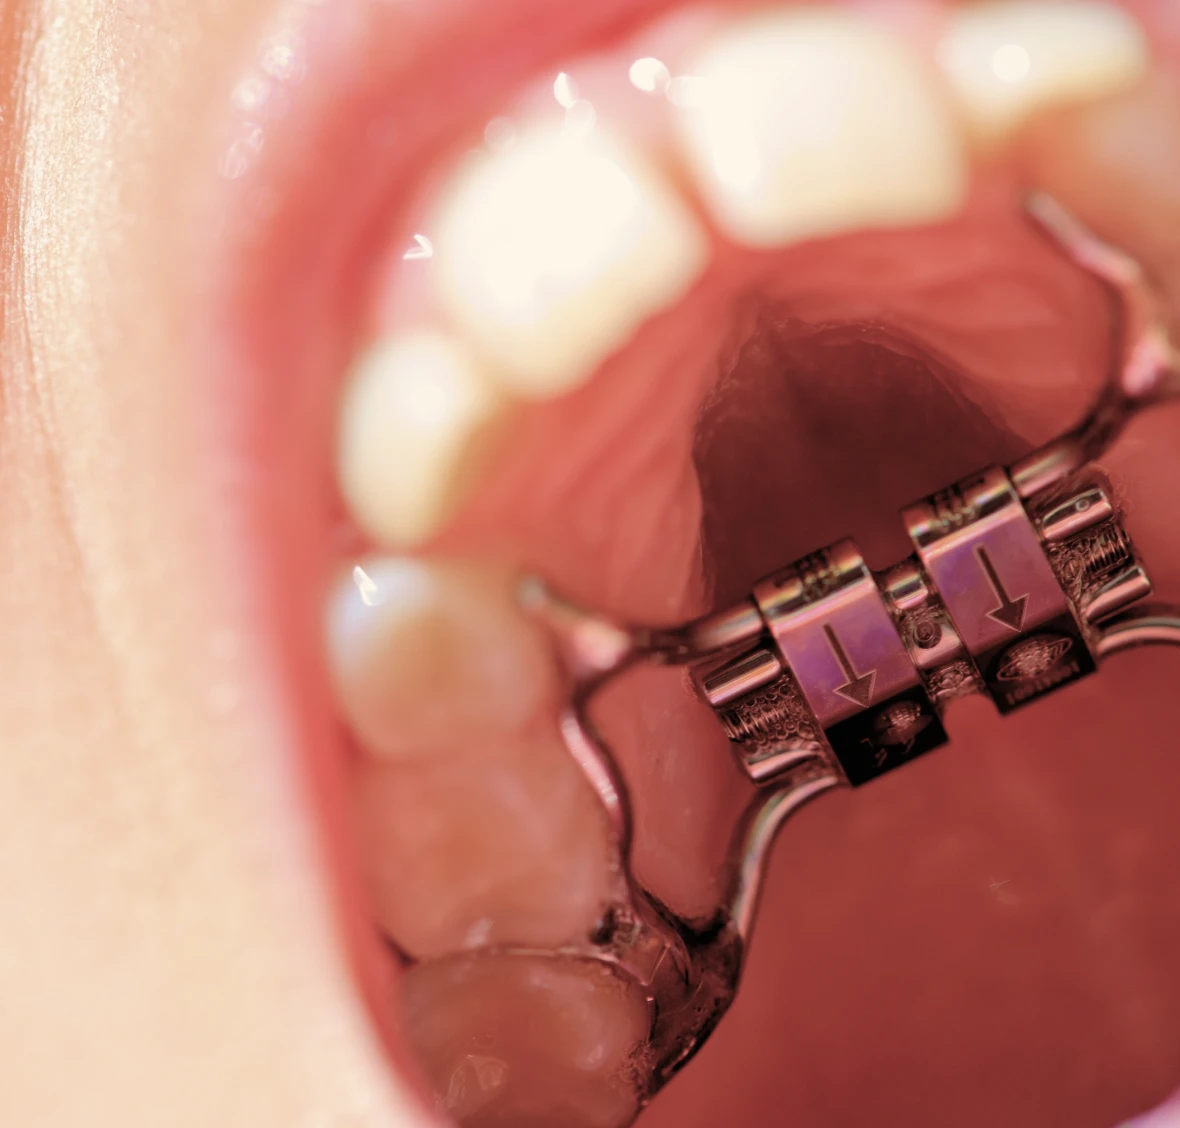

L’orthodontie précoce, appelée également orthodontie interceptive, vise à corriger les problèmes dentaires et fonctionnels dès le plus jeune âge. Elle permet d’accompagner la croissance des mâchoires, d’améliorer la respiration et de prévenir l’aggravation des malpositions dentaires.

Chaque enfant est unique. Le choix du traitement dépend de son âge, de ses habitudes (succion du pouce, respiration buccale, mauvaise déglutition) et du développement de ses dents.